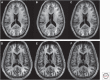

Figure 1.

Typical multiple sclerosis (MS) white matter and gray matter lesions in the brain as shown by cerebral 3T magnetic resonance imaging (MRI). (Left and middle panel) White matter lesions from a 40-year-old woman with relapsing-remitting MS (RRMS), showing 3D sagittal fluid-attenuated inversion recovery (FLAIR, left panel) and 2D axial FLAIR (middle panel). Note the perivenular “Dawson’s fingers” orientation of lesions (arrows, left panel) and numerous periventricular lesions with ovoid/oval predominant configuration on both images. (Right panel) High-resolution FLAIR and a coregistered 3D-modified driven-equilibrium Fourier transform (MDEFT) scans showing a FLAIR hyperintense lesion (arrow) that is MDEFT hypointense (arrow) and involves the cerebral cortex in a 29-year-old man with RRMS.